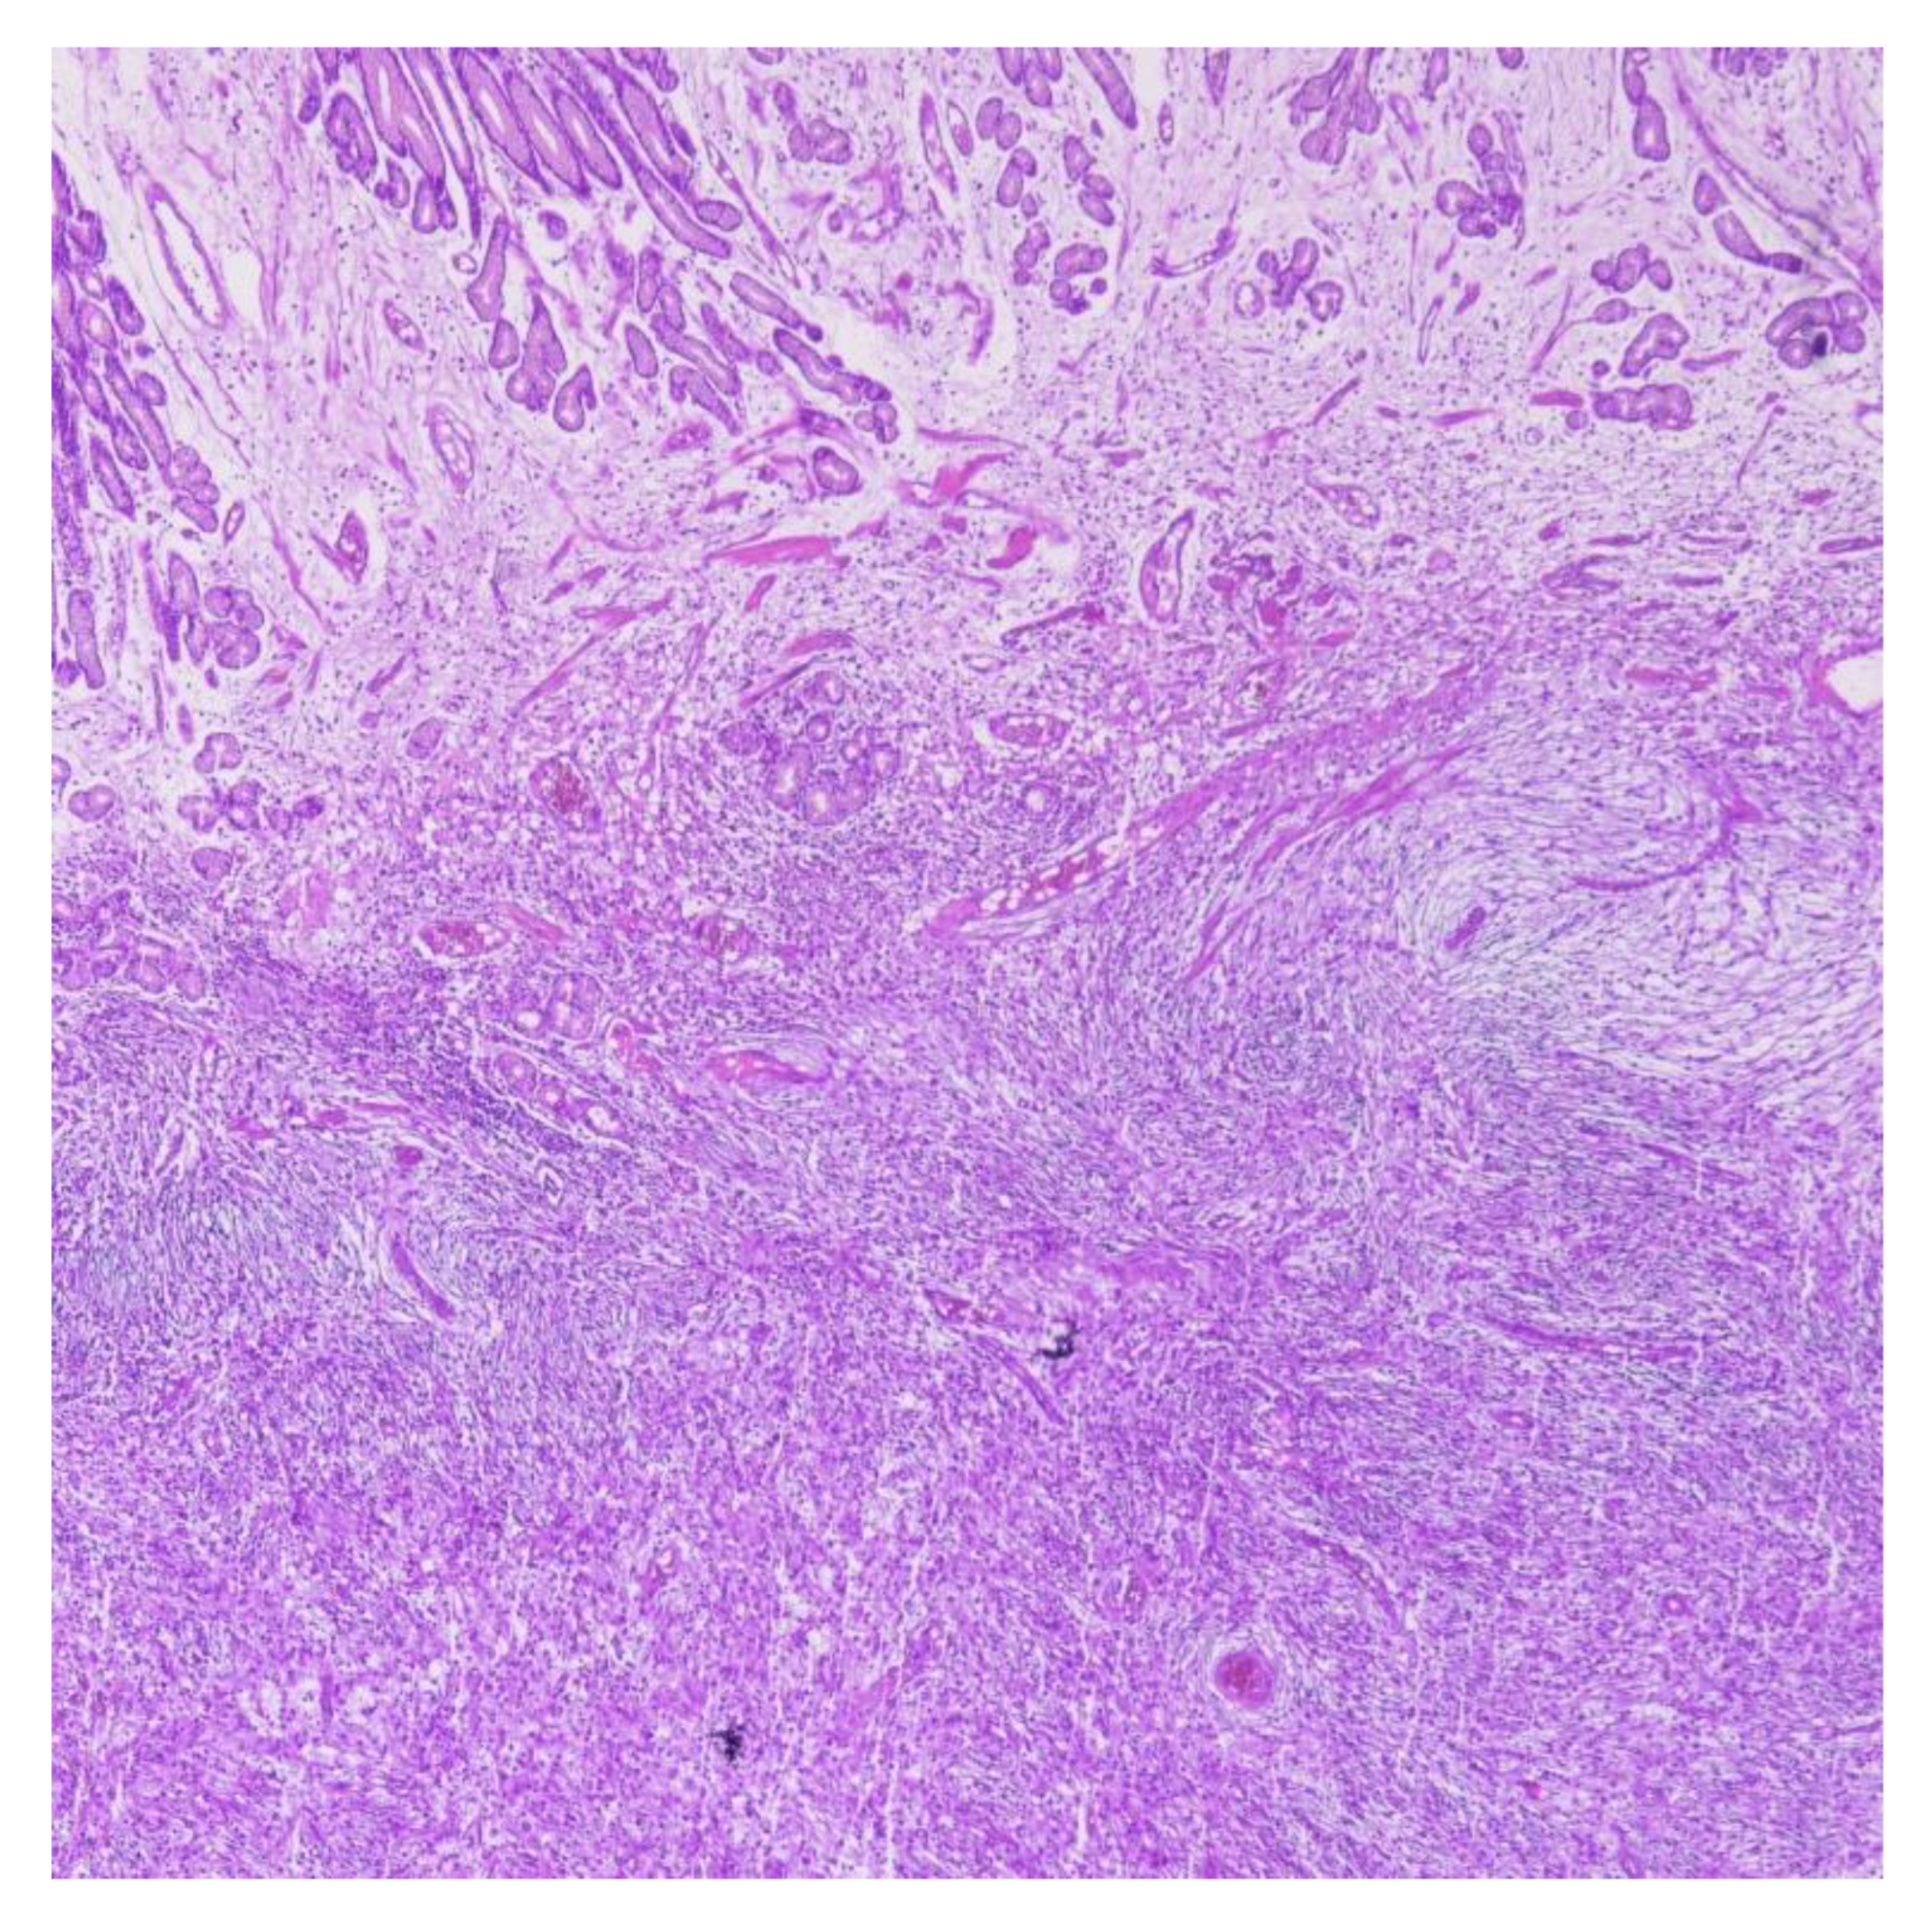

| Inflammatory Fibroid Polyp (IFP/Vanek’s tumor) | Bland spindle/stellate cells in onion-skin perivascular pattern; eosinophil-rich stroma | CD34+, PDGFRA+; CD117–, DOG1–, S100–, Desmin– | Benign, submucosal; may mimic GIST; may rarely cause obstruction or bleeding; PDGFRA mutations common |